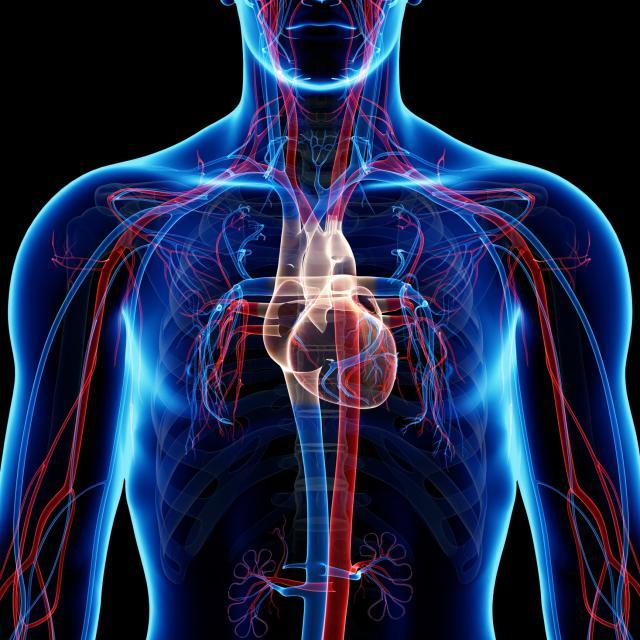

2. SISTEMA CARDIOVASCULAR

1. Indicaciones

1. -Insuficiencia Venosa -Malformación Venosa

2. HIPERTENSIÓN ARTERIAL

1. Tratamiento

1. -Pruebas -Vasidilatadores -Antagonista de Colon -Inhibidores adrenergicos

2. Eje

1. -Primario -Secundiaria -Obesidad -Embarazo

2. Elevación de Presion Sanguinea

3. Examen Físico

1. Piel

1. Uñas

1. Extremidades

1. Venas Yugulares

1. Presión Arterial

1. Pulsos Arteriales

2. Medicamentos

1. Antihipertensivos Anticuagulables

2. Anamnesis

1. -Dolor Torácico -Dolor en extremidades -Palpitación -Tos -Fatiga

2. Factores Determinantes

1. -Tabaquismo -Hipertensión Arterial -Sedentarismo -Obesidad -Diabetes -Estrés -EPOC